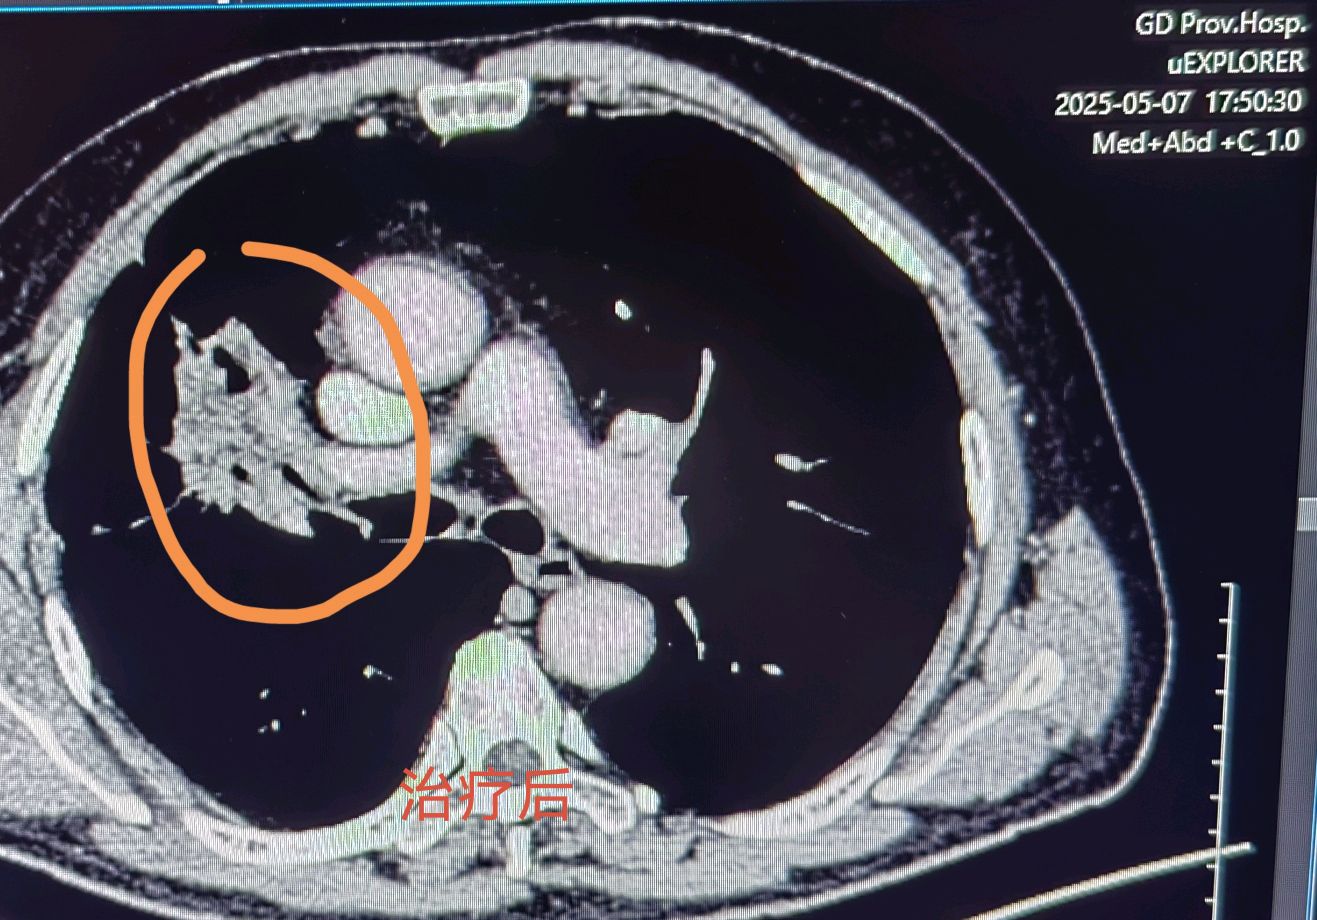

63岁老年男性患者,因为咳嗽伴有血丝痰在当地医院确诊右上肺鳞癌,肿瘤较大侵犯肺动脉暂没有手术机会,在当地医院化疗联合免疫治疗四个疗程后复查肿瘤明显缩小,患者和家属手术愿望强烈,来我门诊就诊复查PET后评估手术还是有机会,遂收入院完善术前检查,顺利完成右中上肺叶切除肺癌根治手术,手术过程顺利,切除彻底干净,术后继续免疫维持治疗,估计会取得不错的预后。